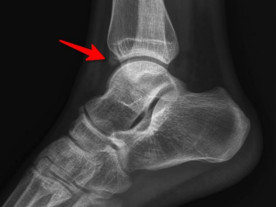

前方長骨刺

踝關(guān)節(jié)鏡見前方長骨刺